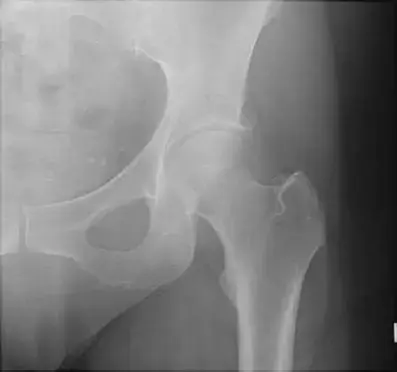

ساركوما العظام: دليلك الشامل للتشخيص والعلاج والتعافي في صنعاء مع الأستاذ الدكتور محمد هطيف

دليلك الشامل لتشخيص وعلاج ساركوما العظام في صنعاء مع الأستاذ الدكتور محمد هطيف. احصل على رعاية متخصصة بأحدث التقنيات الجراحية لضمان أفضل نس…